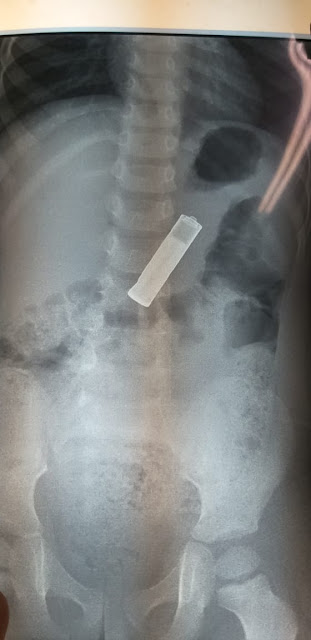

মালদা মেডিকেল কলেজ হাসপাতালে অ্যাসিস্ট্যান্ট প্রফেসর সার্জারি বিভাগের ডাক্তার পার্থপ্রতিম মন্ডল প্রথমে শিশুটিকে দেখে। পরে এক্সরে করা হয় এবং এক্সেরে প্লেট এর মধ্যে ছবিতে ফুটে ওঠে ব্যাটারি ছবি। তার পরই মেডিকেল কলেজ কর্তৃপক্ষ সিদ্ধান্ত নেয় অপারেশন করার। সোমবার রাতে 40 মিনিটের একটি অপারেশন করে মেডিকেল কলেজ ডাক্তাররা। মালদা মেডিকেল কলেজের অ্যাসিস্ট্যান্ট প্রোফেসর ডক্টর পার্থপ্রতিম মন্ডল ব্যাটারি পেটের ভেতর থেকে বার করে। চিকিৎসকরা জানান বাচ্চাটি এখন পুরোপুরি সুস্থ। তবে খেতে একটু অসুবিধা হলেও চিকিৎসকদের মতে রাত থেকে শারীরিকভাবে খাওয়া-দাওয়া করতে পারবে।